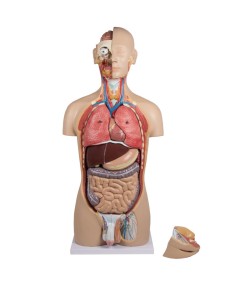

3B Scientific, Torse bisexuel, modèle de luxe, séparable en 20 parties B32

3B Scientific, Torse bisexuel, modèle de luxe, séparable en 20 parties B32

3B Scientifique, torse bisexuel japonais, décomposable en 18 parties B32/4

3B Torse scientifique, africain bisexuel, décomposable en 24 parties B37

3B Scientific, mini torse humain sans tête, décomposable en 9 parties B20

Découvrez le monde de l'anatomie avec des modèles anatomiques de précision

Bienvenue sur Tuttoanatomia.it, le portail de référence en Italie pour l'achat de modèles anatomiques, de posters, de lits portables, de simulateurs médicaux et de littérature spécialisée. Grâce à nos modèles anatomiques de pointe de 3B Scientific et Erler Zimmer, nous offrons une expérience d'apprentissage inégalée.

Du crâne en 22 parties à verrouillage magnétique aux modèles de colonne vertébrale, des modèles d'articulation aux modèles de cœur, chaque pièce de notre collection est conçue pour une immersion totale dans l'étude de l'anatomie humaine. Nos modèles, réalisés à partir de scans d'os réels, garantissent une expérience tactile authentique et une fidélité de poids presque identique aux originaux.

Indispensables aux étudiants comme aux professionnels, nos modèles anatomiques sont des outils pédagogiques qui permettent d'observer les structures anatomiques avec précision, en évitant les dissections ou les études invasives. Ils sont également utiles pour expliquer les pathologies aux patients, ce qui rend la communication plus efficace et permet de gagner un temps précieux.